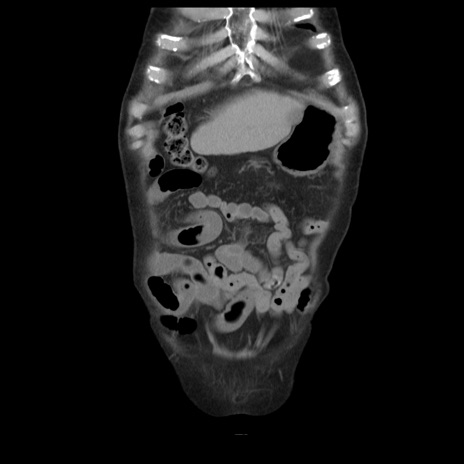

症例21(冠状断像)

【症例】70歳代男性

【主訴】腹痛

【現病歴】肝硬変・肝細胞癌にてかかりつけの方。約9時間前に食後より腹痛出現。症状が徐々に増悪し、嘔吐出現したため来院。

【既往歴】肝硬変、肝細胞癌(RFA、TACE後)

【身体所見】意識清明、表情苦悶様、BT 36℃、BP 129/78mmHg、P 88bpm、SpO2 97%(RA)、右上腹部から心窩部にかけて圧痛あり、反跳痛なし、筋性防御あり。

【データ】WBC 5800、CRP 0.16